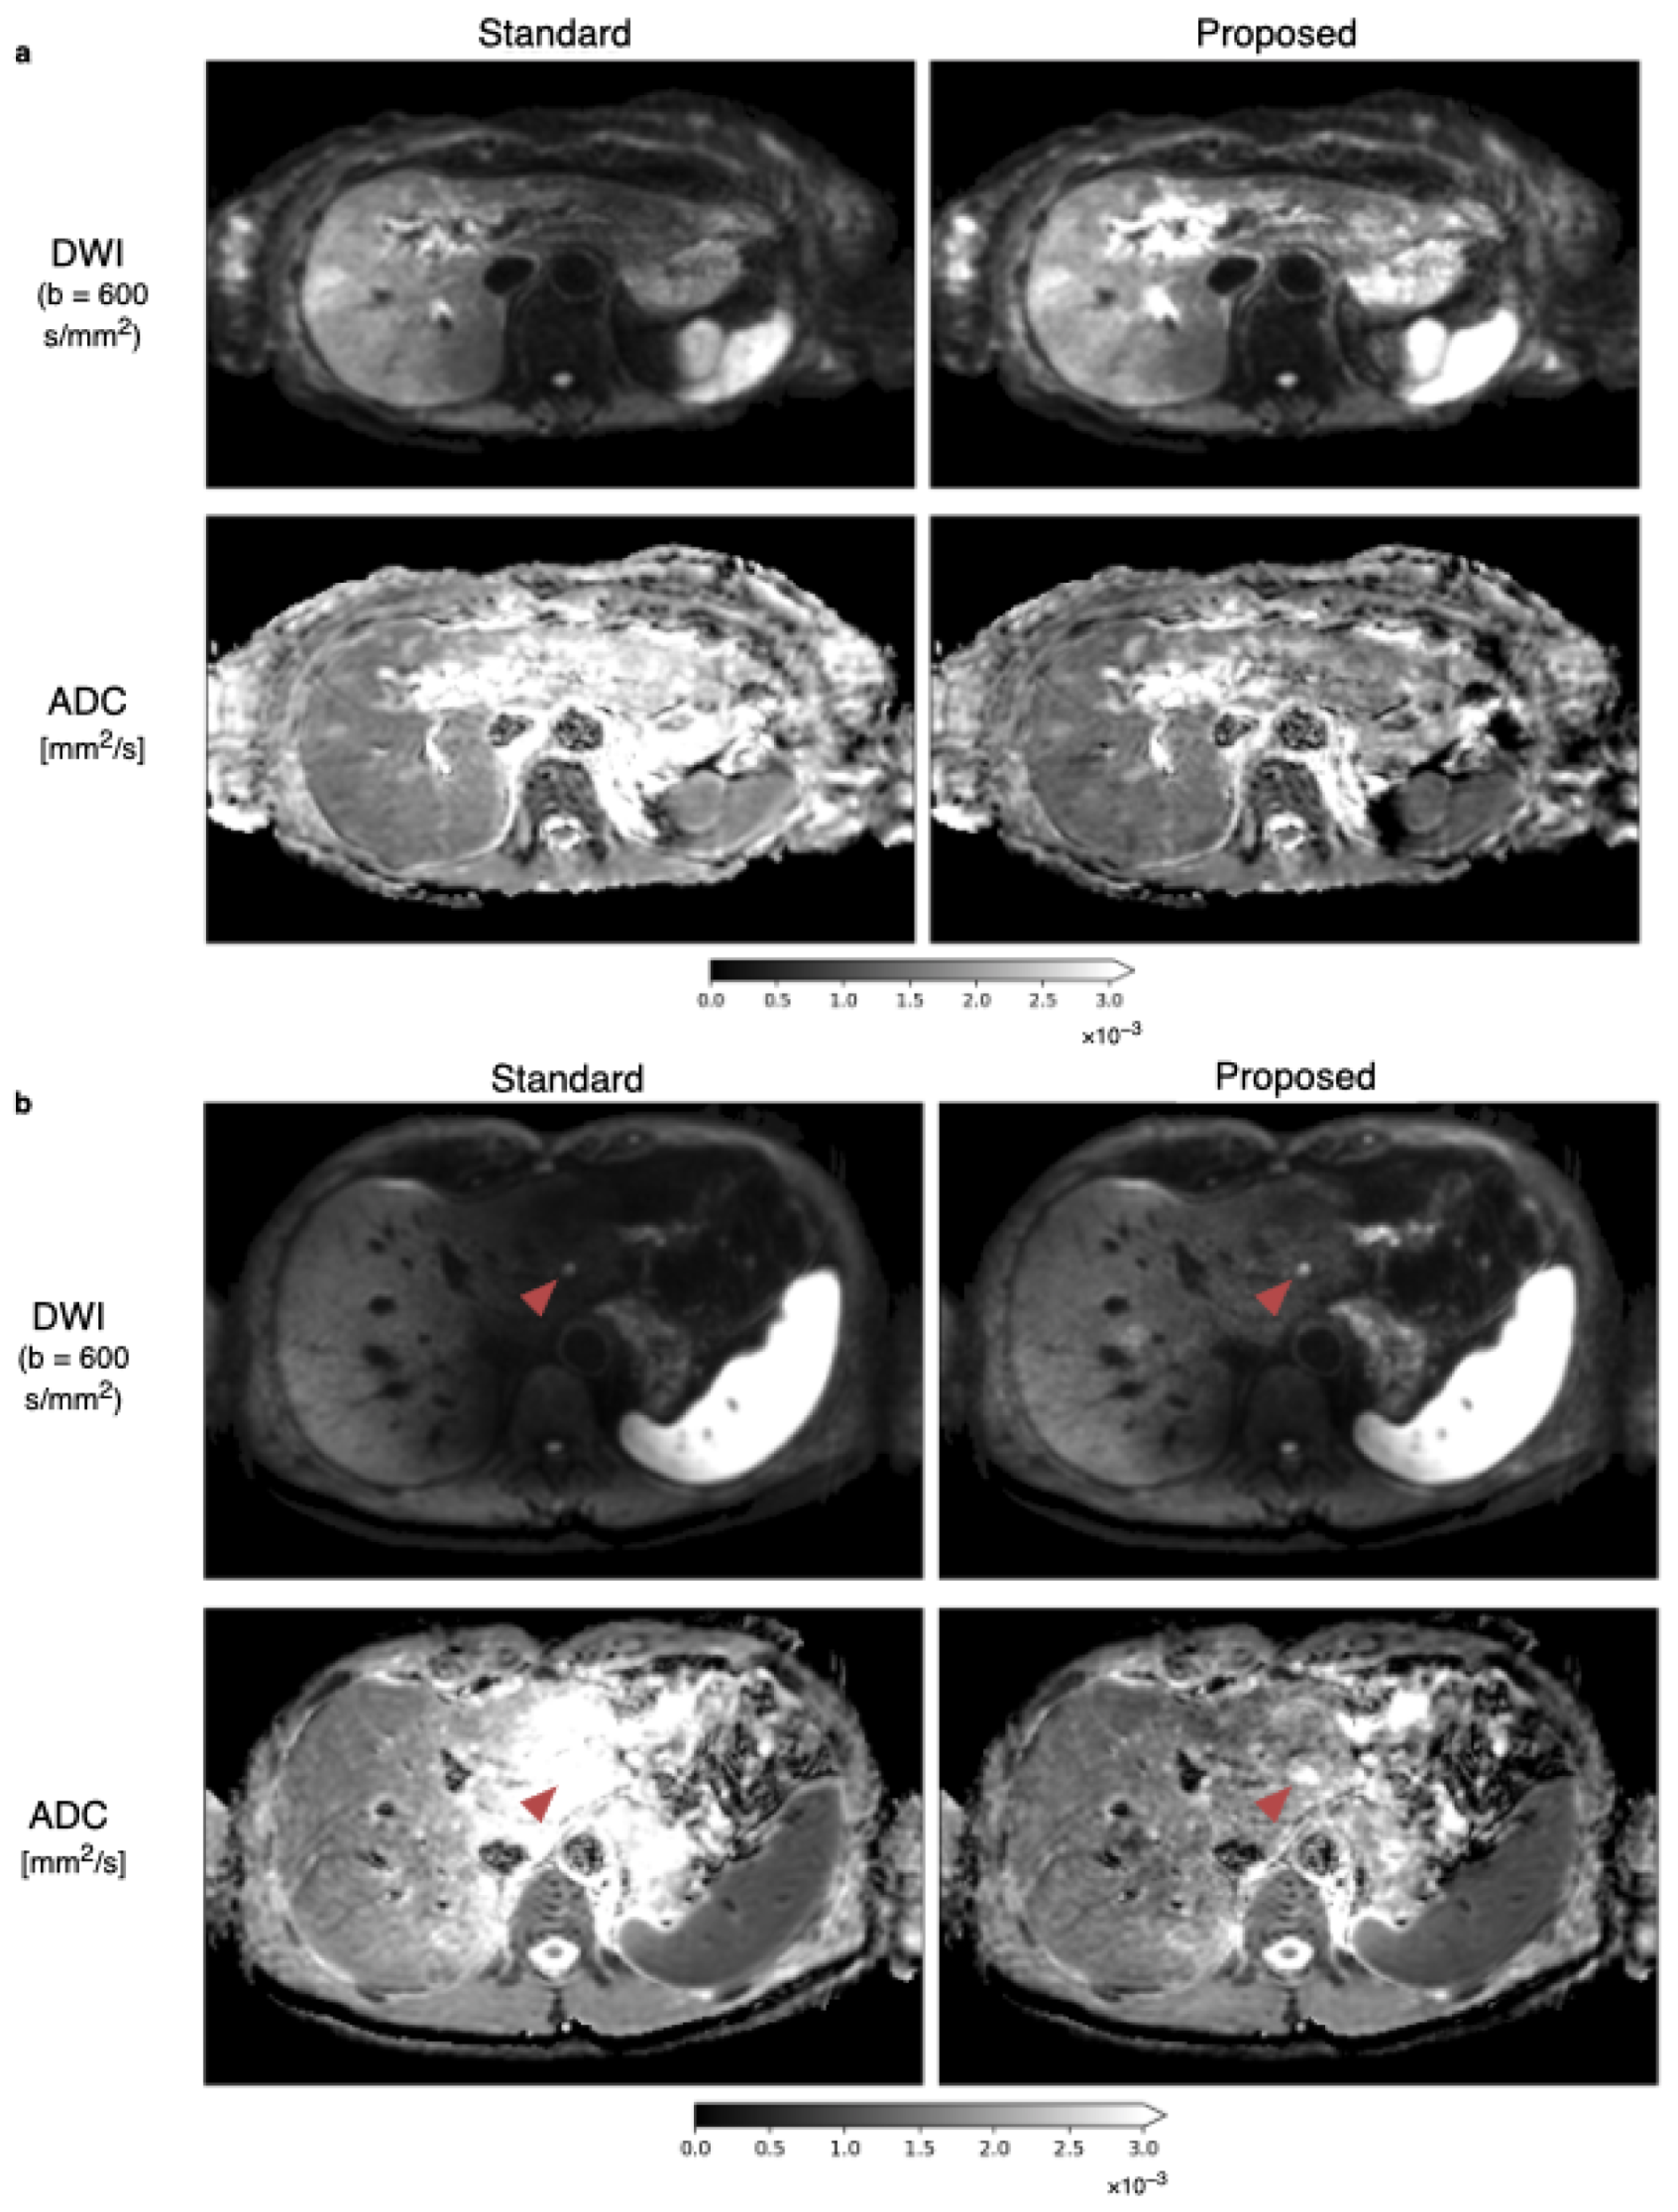

3.2. Spatial Scaling of Average DWI

3.3. Quantitative ADC Measurement

3.4. Radiological Reading